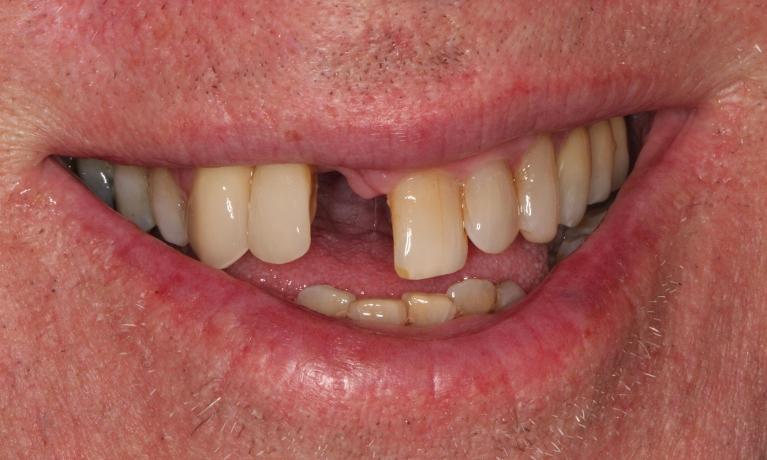

This young dad had four congenitally missing upper teeth. He had a quick orthodontic treatment and a large span bridge placed in as a teenager. He never smiles with teeth showing.

After many years of wear and tear, some of the work started to break and fail. We removed the defective bridges, managed to save all the existing teeth and placed four implant supported crowns in. The patient is very happy to be able to smile confidently now.